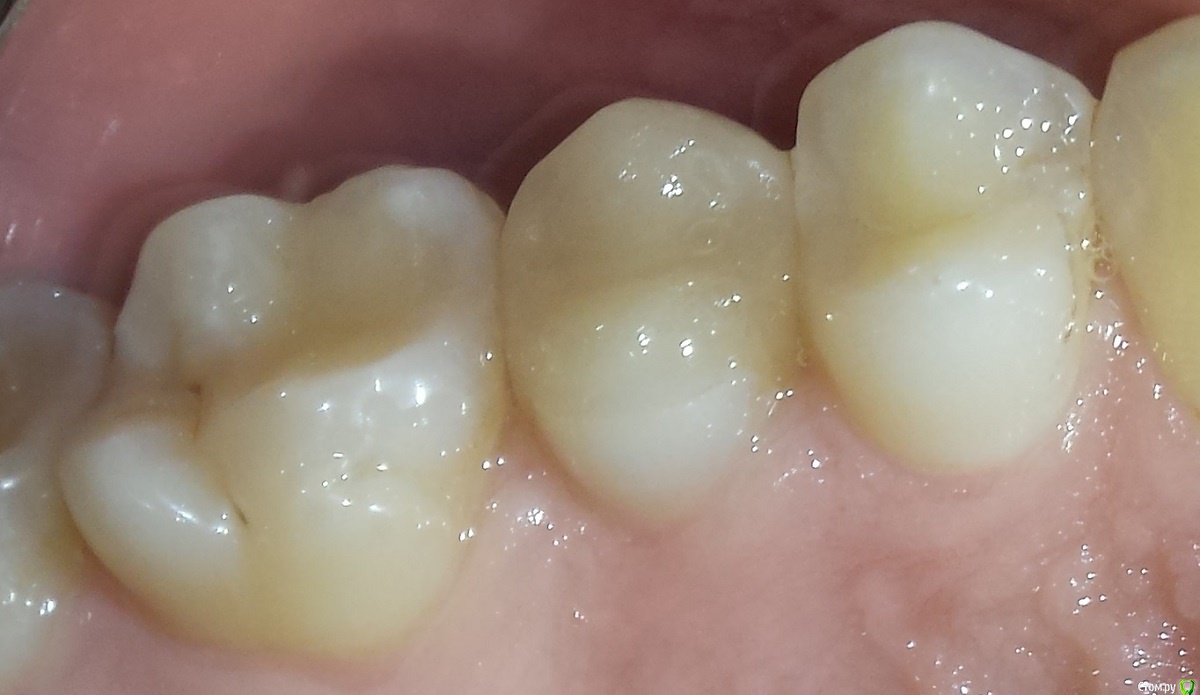

IvanStepanovich Опубликовано 23 марта, 2017 Поделиться Опубликовано 23 марта, 2017 Добрый день, имеется зуб – депульпированный второй премоляр слева сверху. После лечения каналов зуб был обточен под эндокоронку Cerec Empress. В настоящий момент жалоб и болей нет, зуб никак не беспокоит. Но эту конструкцию хочу заменить т.к. не нравится шероховатость жевательной поверхности и форма реставрации.Будет ли установка новой эндокоронки наиболее адекватным средством восстановлением моего зуба? Или же в моем случае коронка (с культевой вкладкой или композитом) будет лучшим решением? Спасибо. Ссылка на комментарий

IvanStepanovich Опубликовано 23 марта, 2017 Автор Поделиться Опубликовано 23 марта, 2017 Зуб был пролечен и восстановлен в январе 16г, сразу после фиксации все было ОК, не было никаких шероховатостей. Через пару недель в этом зубе появилась боль (тупого характера, ближе к корню, боль лишь при накусывании), доктор сказал, что вкладка возможно чуть завышает прикус и подпилил ее прямо во рту (между снятием слепка и фиксацией вкладки были заменены 2 реставрации - одна на 2 моляре справа снизу, вторая на 1 моляре слева сверху). Сразу после первого подпиливания (начало-середина февраля 2016) боль в зубе утихла, однако временами все же была (боль тупого, ноющего характера в районе корня зуба, эпизодически при жевании), где-то в апреле-мае 2016 тот же доктор вновь мне подпилил эту вкладку, с тех пор зуб не беспокоит никак. Делали снимок в конце 2016г, по словам врача (он же лечил каналы и подпиливал эту вкладку) с каналом зуба все хорошо, и что вроде как все предыдущие боли были вызваны перегрузкой зуба из-за того, что вкладка завышала прикус. Сейчас кроме собственно формы и шероховатости жалоб нет. Ссылка на комментарий